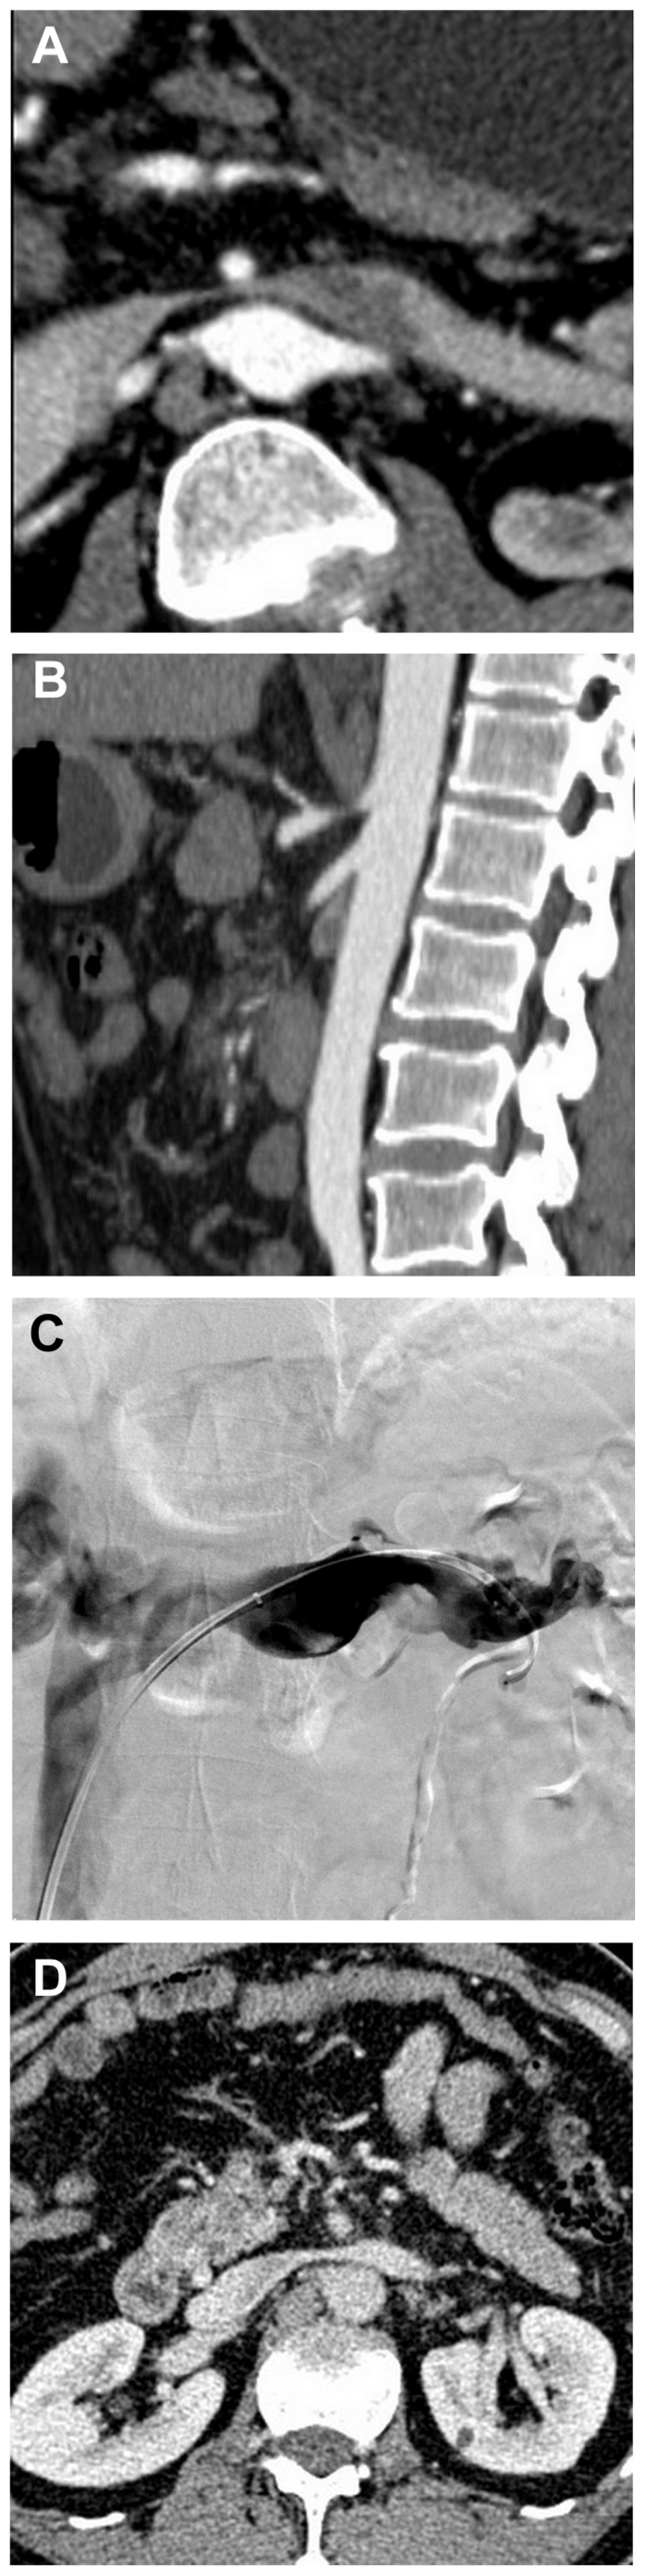

Left renal vein thrombosis with nutcracker syndrome.